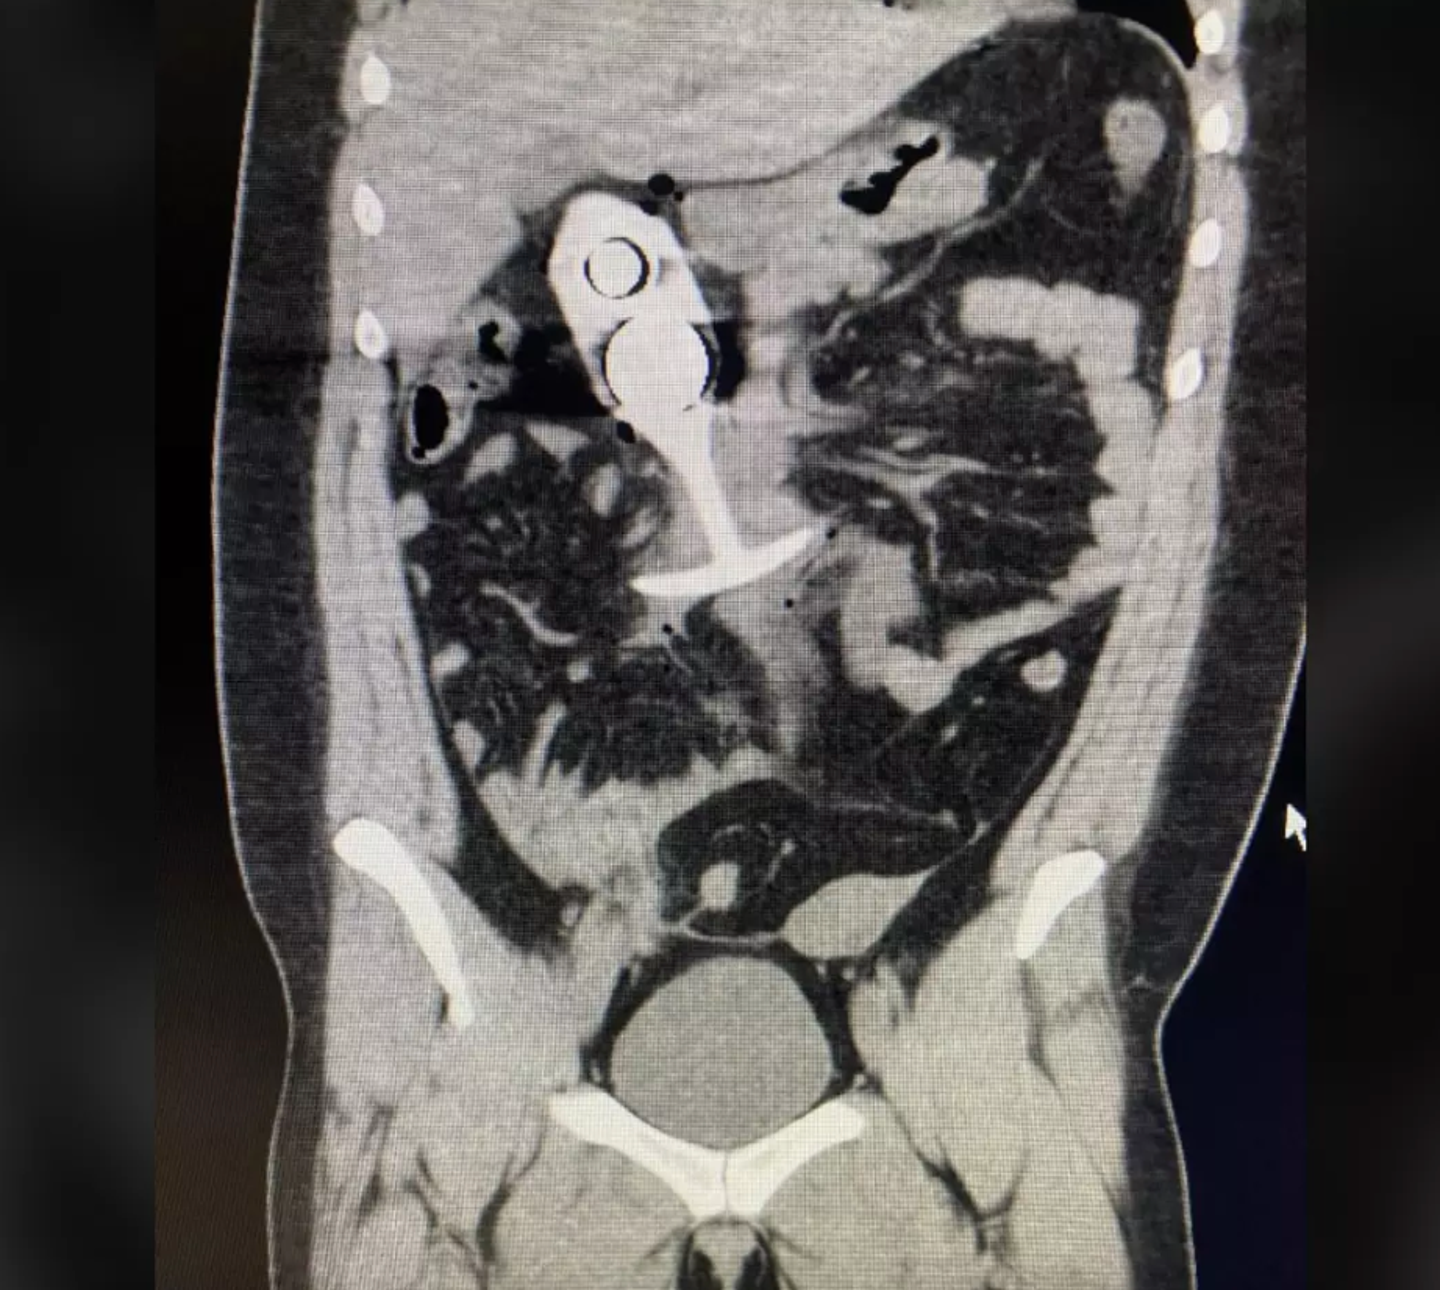

Not long after, a picture appeared on Reddit that many users claimed came from the woman’s MRI scan. The image seemed to show the object inside the body. However, no official confirmation has ever been given that the photo was directly connected to this particular case.